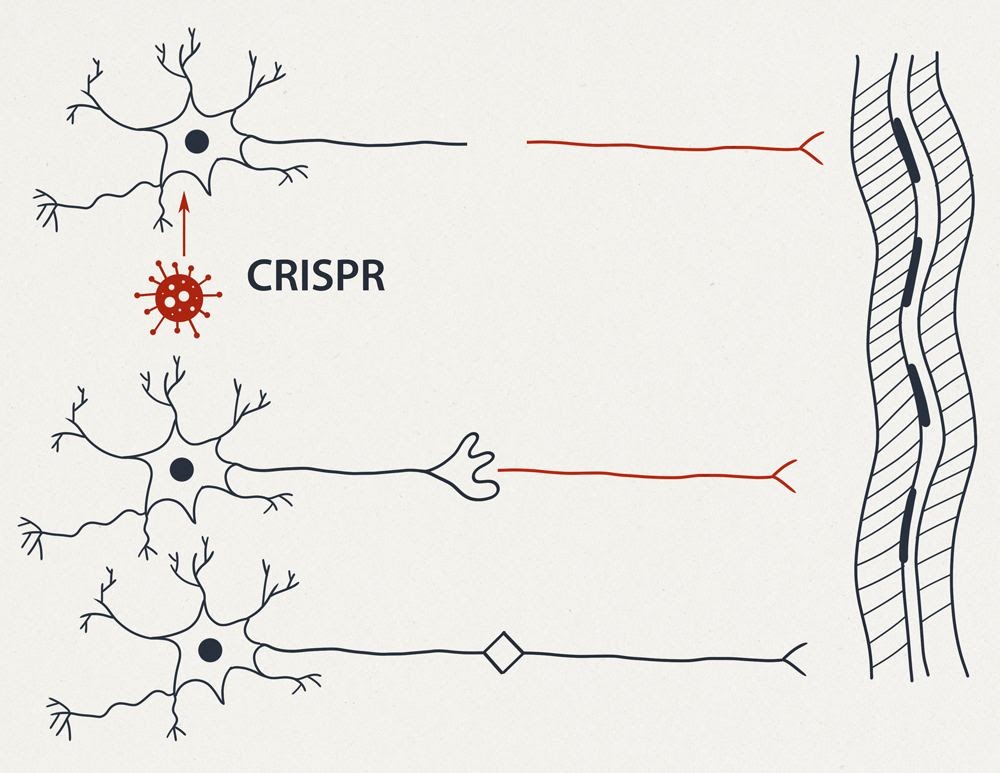

На рисунке 1 (см. выше) схематично представлены:

-

Справа – вертикально многоядерный фрагмент поперечнополосатой мышцы.

-

Вверху – две схемы “типичных нейронов”: можно обратить внимание на то что форма отростков второго нейрона – называется “Т-образной”.

-

Далее схематично изображен “топор”, перерубающий нерв или спинной мозг и отсекающий от одного из пострадавших нейронов фрагмент длинного отростка аксона. Фрагмент клетки, лишённый ядра, и многих других жизненно важных частей стойко теряет свои функции и способность к регенерации.

-

В нижней части рисунка изображен “нейрон будущего”, имеющий на периферии второе запасное ядро.

На рисунке 2 (см. выше) изображены:

-

травма наносимая генномодифицированному нейрону.

-

Ниже представлены два варианта сращения двух образовавшихся нейронов. В центре – “простое сращение” несколькими синапсами.

-

В нижней части: каждый из получившихся в результате травмы одноядерных нейронов происходит “незавершенный” митоз – без телофазы, в результате чего с каждой стороны образуются по два ядра. По одному из этих новых ядер направляются в зону повреждения, где образуется дендритная сеть синаптических контактов. Данная сеть в дальнейшем перестраивается под действием тренировок с возможностью формирования дополнительного усилителя или фильтра-преобразователя сигналов.